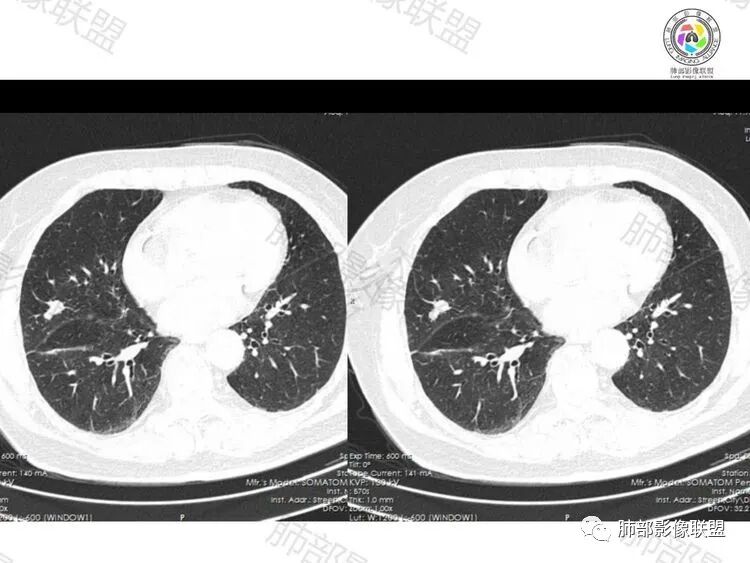

右肺中叶结节,似多结节融合,伴索条,叶间裂牵拉,周围卫星灶,串珠影?六个核桃?考虑隐球,鉴别腺癌

右肺中叶结节,呈不规则状,似多结节堆积感觉,边缘膨隆分叶,周围长毛刺,临近叶间胸膜牵拉,重建显示支气管有截断,首先考虑恶性,腺癌,鉴别隐球

老年女性患者,右肺中叶不规则结节灶,边界清晰、平直,内部密度均匀,两个结节有融合趋势,胸膜有牵拉,支气管有堵塞,考虑炎性,隐球菌可能,鉴别腺癌

女,74,右上腹隐痛不适30年,以胆囊炎入院。胸部CT:右肺中叶叶裂旁实性结节,边缘清楚,部分膨隆,部分平直,似由两个病灶融合,邻近支气管有截断、有穿行,邻近叶裂牵拉,叶裂似有多个结节,看不清,血管集束,脐凹?考虑:IAC?两子灶融合,鉴别PC、TB等。

叶间胸膜下结节,边缘条索影,周围及叶间胸膜多发粟粒样小结节,支持炎性结节,隐球,结核或者慢性非特异性炎症。

第一感觉隐球菌,因为旁边有一个兄弟,支气管远端堵塞,鉴别结核和腺癌